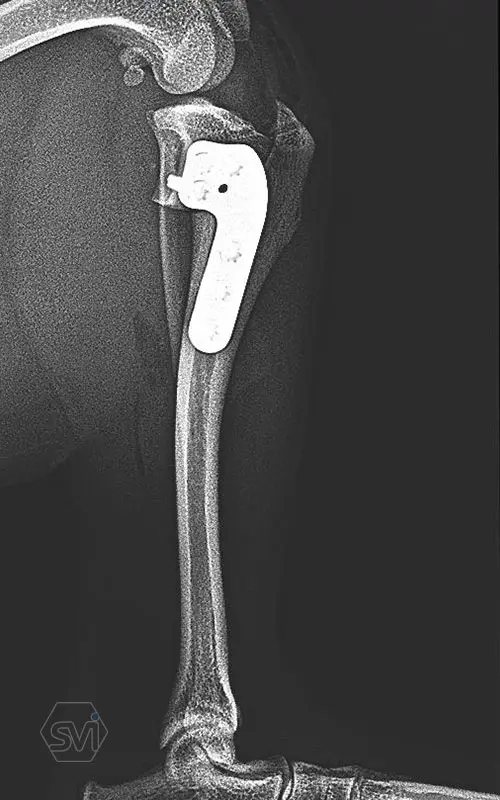

Introducing the precontured polyaxial locking TPLO family, now available in all sizes:

- Mini: 2.0mm (thinner and thicker version)

- Midi: 2.4mm

- Small: 2.7mm

- Standard: 3.5mm (both in short and extended versions)

- Giant: designed for 4.0mm screws.

It has a number of advantageous features that make it stand out from standard TPLO solutions:

- well designed that follows the anatomical position and ideal hole placement

- precontoured, its use shortens the surgical time, no greater physical force is required for bending

- locking system for greater stability

- polyaxial screw insertion, the direction of screw insertion can be freely selected in a 30-degree circle while maintaining angular stability! (this is very useful to avoid driving the screw into the joint, and the temporary fixing can also be avoided with a K-wire)